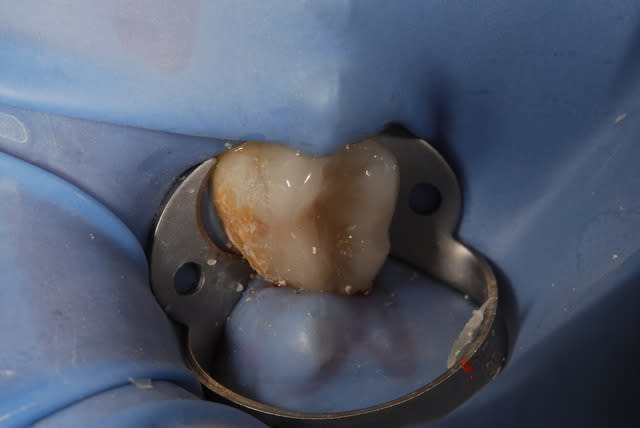

Oui .(photos 2 et 3 d'hier)